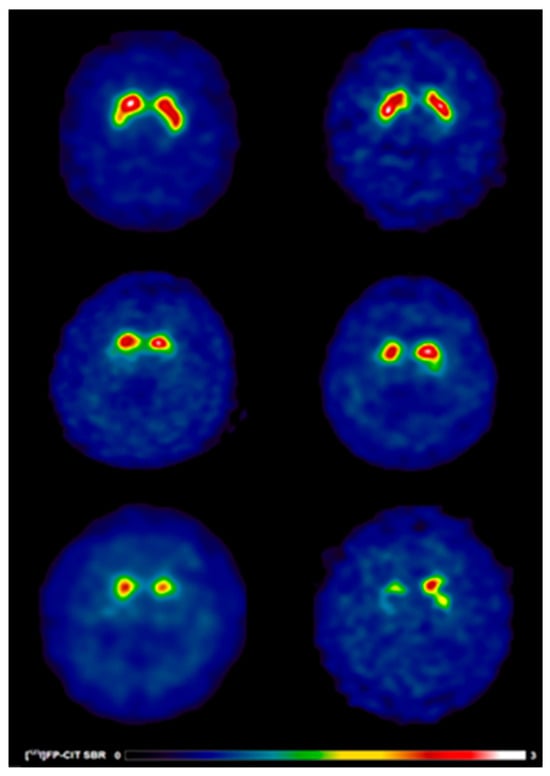

[123I]FP-CIT SBR Values

[123I]FP-CIT SBR

| [123I]FP-CIT SBR | |||

| contralateral_caudate [mean (±SD)] | 1.71 (±0.5) | 1.88 (±0.5) | 0.002 |

| ipsilateral_caudate [mean (±SD)] | 1.97 (±0.5) | 2.24 (±0.5) | <0.001 |

| mean_caudate [mean (±SD)] | 1.84 (±1.8) | 2.06 (±0.5) | <0.001 |

| contralateral _putamen [mean (±SD)] | 0.63 (±0.2) | 0.72 (±0.2) | <0.001 |

| ipsilateral _putamen [mean (±SD)] | 0.83 (±0.2) | 1.03 (±0.3) | <0.001 |

| mean_putamen [mean (±SD)] | 0.73 (±0.2) | 0.87 (±0.2) | <0.001 |

| contralateral _striatum [mean (±SD)] | 2.34 (±0.6) | 2.60 (±0.7) | <0.001 |

| ipsilateral _striatum [mean (±SD)] | 2.81 (±0.8) | 3.27 (±0.8) | <0.001 |

| mean_striatum [mean (±SD)] | 1.29 (±0.3) | 1.46 (±0.3) | <0.001 |

| [123I]FP-CIT SBR * | |||

| contralateral_caudate [mean (±SD)] | 1.39 (±0.4) | 1.58 (±0.4) a | 0.02 |

| ipsilateral_caudate [mean (±SD)] | 1.67 (±0.5) | 1.88 (±0.5) a | 0.02 |

| mean_caudate [mean (±SD)] | 1.53 (±0.4) | 1.73 (±0.4) a | 0.01 |

| contralateral _putamen [mean (±SD)] | 0.51 (±0.1) | 0.60 (±0.1) a | 0.003 |

| ipsilateral _putamen [mean (±SD)] | 0.66 (±0.2) | 0.78 (±0.2) a | 0.008 |

| mean_putamen [mean (±SD)] | 0.58 (±0.1) | 0.69 (±0.1) a | 0.002 |

| contralateral _striatum [mean (±SD)] | 1.90 (±0.5) | 2.18 (±0.6) a | 0.008 |

| ipsilateral _striatum [mean (±SD)] | 2.33 (±0.7) | 2.66 (±0.7) a | 0.01 |

| mean_striatum [mean (±SD)] | 1.06 (±0.3) | 1.21 (±0.3 ) a | 0.007 |